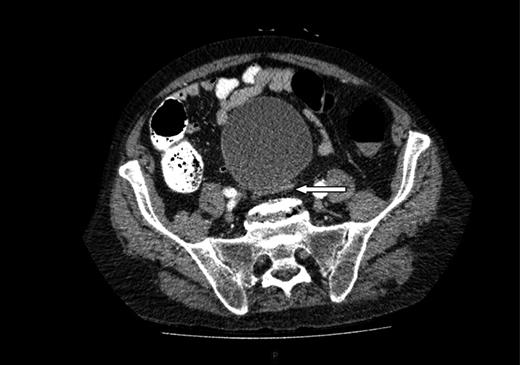

This time he was tachycardic and hypotensive with a much less distended but tender abdomen and still no palpable pulsatile masses. He was clinically stable enough to undergo a further CT scan of the abdomen and pelvis, now revealing a ruptured AAA (Fig. 4). We immediately transferred the patient to the regional hospital where he underwent emergency endovascular aneurysm repair on the same day.

Repeat CT scan of the abdomen, showing evidence of a contained rupture.